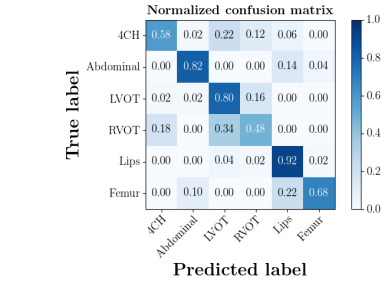

We further compare the performance of MIDNet with and without unlabeled data on the target domain. Here, the with unlabeled data setting utilizes the training data containing labeled data and unlabeled data, while the without unlabeled data setting only uses the labeled data. The confusion matrices in Fig. 8(a) show the effectiveness of unlabeled data in the proposed method, for example, the classification accuracy of in MIDNet (e.g., 4CH and Lips) improves when integrating unlabeled data.

| With unlabeled data | Without unlabeled data |

|

|